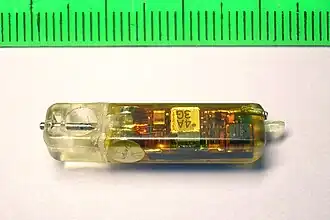

Внутрижелудочная pH-метрия играет важнейшую роль при диагностике и лечении кислотозависимых заболеваний, при исследовании гастроэзофагеальных, дуоденогастральных, фаринголарингеальных рефлюксов. В клинической практике нашли применение несколько методов внутрижелудочной pH-метрии:эндоскопическая (длительность измерений 5 минут), экспресс-pH-метрия (около 30 минут), кратковременная стимулированная (до 2—3 часов) и длительная (24 часа и более) pH-метрия. pH-метрия также применяется для оценки действия кислотоподавляющих препаратов. Измерения выполняется с помощью специальных pH-метрических зондов, вводимых пациенту перорально (при кратковременной pH-метрии), трансназально (при суточной pH-метрии)[21][23], через инструментальный канал эндоскопа (при эндоскопической pH-метрии)[24] или с помощью прикрепляемых к стенке пищевода pH-метрических капсул[25]. Исследование некислых рефлюксов выполняется с помощью импеданс-pH-метрии пищевода[26]. Для дифференциальной диагностики загрудинных болей неясной этиологии применяется гастрокардиомониторинг — одновременное исследование кислотности ЖКТ и электрокардиограммы[21].

pH-грамма желудка при подборе ингибиторов протонной помпы Прикрепляемая к стенке пищевода капсула «Bravo» для исследования ГЭР

Прикрепляемая к стенке пищевода капсула «Bravo» для исследования ГЭР